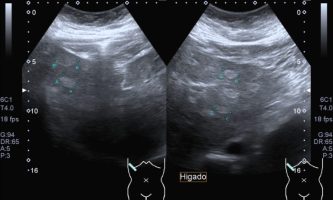

El médico de referencia le indica nueva ecografía de control, donde se observan múltiples y extensas lesiones focales hepáticas hiperecogénicas, redondeadas y confluentes, las cuales predominan en adyacencia a venas supra hepáticas, sin condicionar efecto de masa y sin alteración de la superficie hepática(fig. 1 y 2). Ante la valoración con Doppler color no presenta patrón de flujo peri ni intralesional y respeta el calibre de las venas supra hepáticas(fig. 3 y 4). Dada las características ecográficas se sospecha esteatosis focal multinodular confluente como principal diagnóstico presuntivo, siendo los diagnósticos diferenciales patologías de naturaleza infecciosa, tumoral o metastásica.